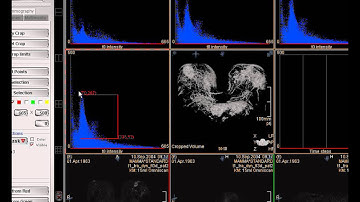

The DCE Tool; DCE CT Analysis Tutorial, Webcast Part 1